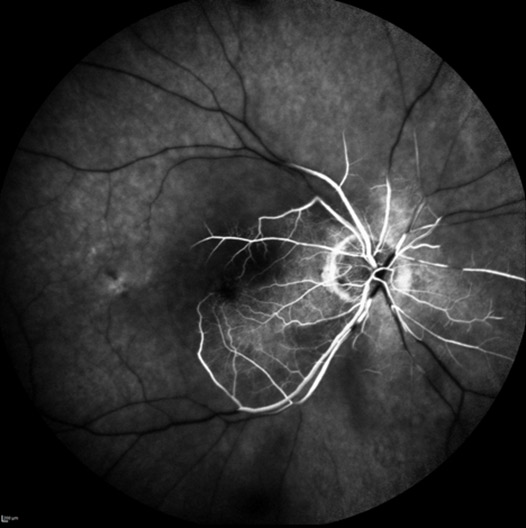

A 80-year-old female experimented nasal visual field loss in her right eye (OD) with preserved temporal visual field. Her past medical history was significant for age-related macular degeneration and hypertension. Best-corrected visual acuity was 6/6 OD and 6/9 OS. A pupillary afferent defect was present OD. Slip lamp examination was unremarkable in both eyes. Fundus examination OD revealed a whitened posterior pole with sparing in the papillomacular bundle. Spectral-domain optical coherence tomography OD revealed inner retinal hyperreflectivity with fovea sparing (Fig 1A). Fluorescein angiography showed a central retinal artery occlusion (CRAO) with cilioretinal sparing OD (Fig 1B).

Cilioretinal artery is an anatomic variant found in 15 to 30% of the population that often supplies the papillomacular bundle, but that supplies the foveola in only 10% of eyes1, 2. Therefore, its presence and specifically its distribution makes it possible of maintaining central vision in the event of a CRAO2, 3, 4.